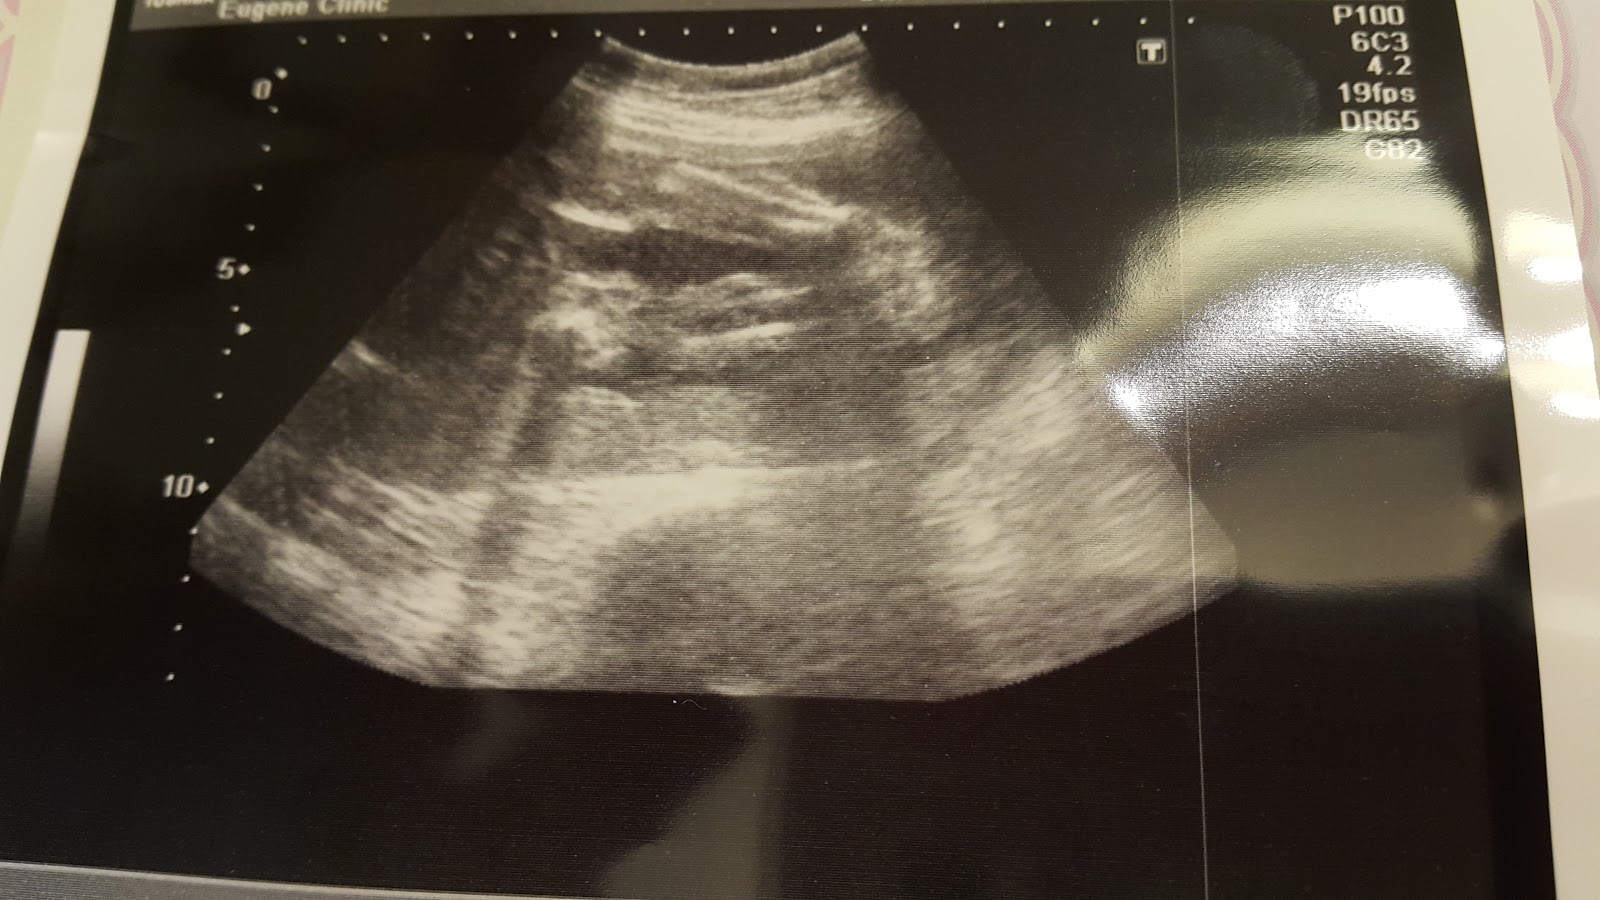

雖然已經是第二胎了,但超音波照片仍是讀不太懂

當下醫生解釋時覺得都看的懂,很簡單啊!

但要寫記錄時,就霧煞煞了,冏。

第一張照片當下跟Leo說,這是妹妹的腳

但今天看應該是手才對吧?!

好冏歐!看不出來~

每次醫生一定會照的腦袋瓜

接著說一些成長數據等

baby都有好好長大耶

現在大約780g,跟懷孕週數相符

脊椎也是醫生每次會照的地方